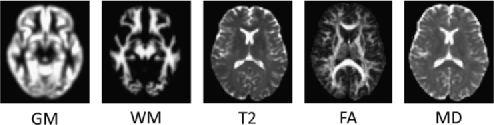

For this analysis, whole-brain (unmodulated) GM and WM images derived from the SPGR scans, the T2 structural images plus the FA and MD images derived from the DTI sequence were used for classification, yielding a total of five distinct modalities for each subject. For illustrative purposes, an example of each type of image after preprocessing is provided in Figure 1.

Refer to caption

Figure 1: Examples of each data source (after preprocessing), taken from the same slice and subject.